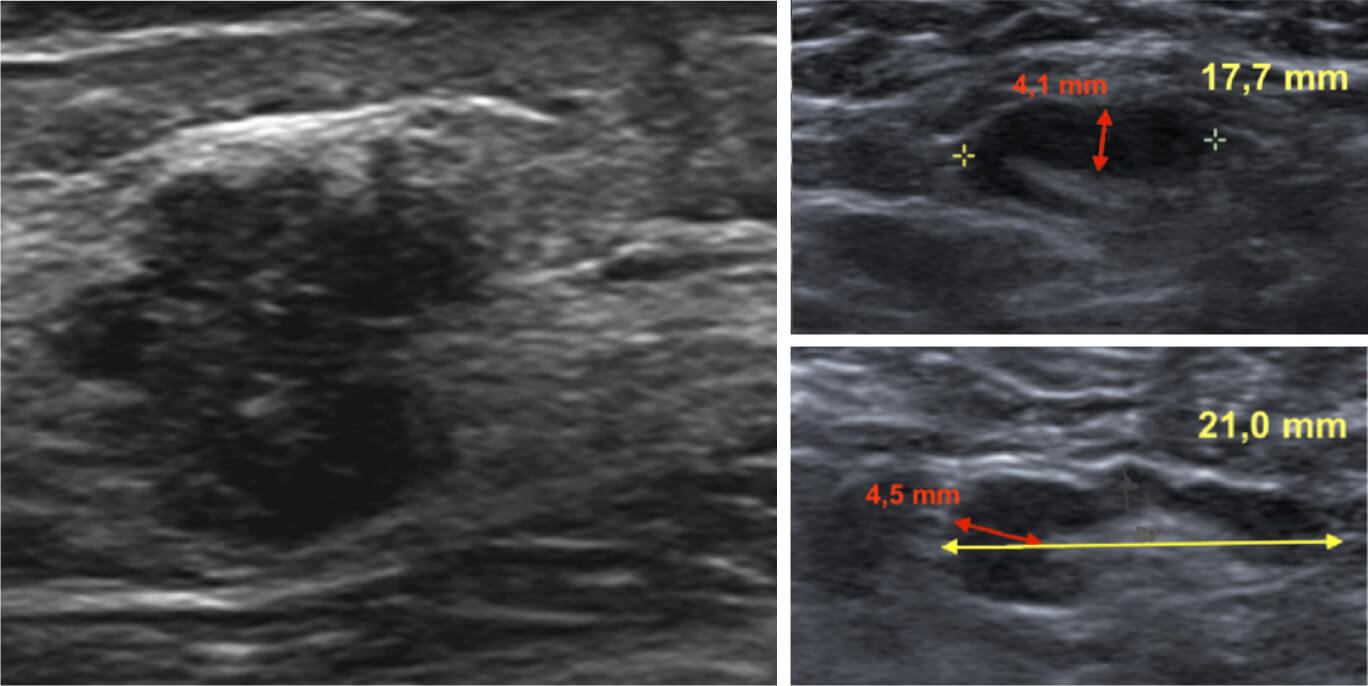

Результаты компьютерной томографии органов грудной клетки, брюшной полости и малого таза с внутривенным контрастированием убеждают вас в наличии у пациентки диссеминированного характера заболевания с метастатическим поражением костей:

Рис. 2 — МСКТ органов малого таза с внутривенным контрастированием. Отмечается литическое поражение левой вертлужной впадины, правой вертлужной впадины, проксимального отдела бедренной кости.

Картина смешанного (бластического и литического) поражения была обнаружена в зоне крестца и в области поясничного отдела позвоночника:

Рис. 3 — МСКТ органов малого таза с внутривенным контрастированием. Отмечается литическое и склеротическое поражение скелета области крестца и поясничного отдела позвоночника.